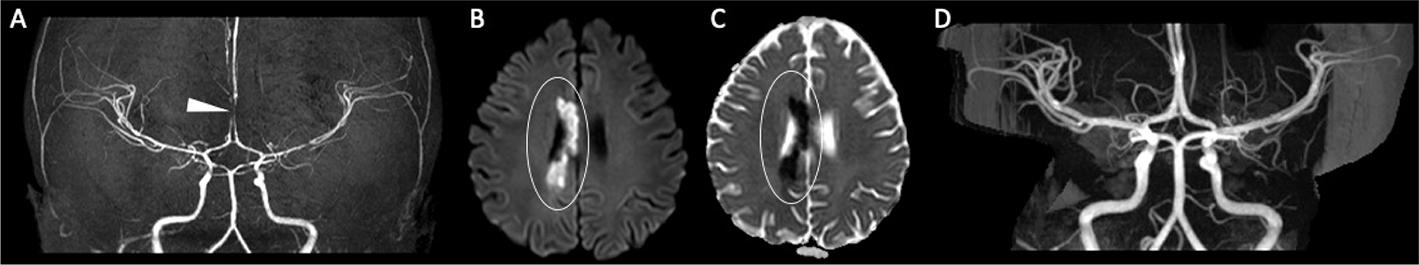

Fig 2

Figure 2. A six-year-old female with B-ALL receiving intrathecal methotrexate and Cerubidine, presenting with new left facial palsy. MR angiography (A) demonstrates multifocal stenosis of the intracranial arteries, most severe along the right ACA (white arrowhead), likely representing vasculitis. DWI (B) and corresponding ADC map (C) demonstrate diffusion restriction along the right aspect of the corpus callosum and paramedian frontal and parietal lobes (white circle). Follow-up MRA (D) demonstrates resolution of arterial stenoses.